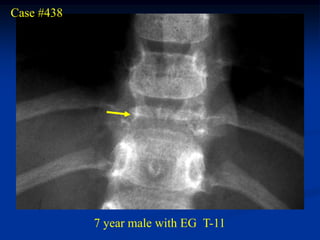

Case #438

7 year male with EG T-11

Sagittal gad contrast MRI

Sagittal T-2 MRI showing protrusion into vertebral canal